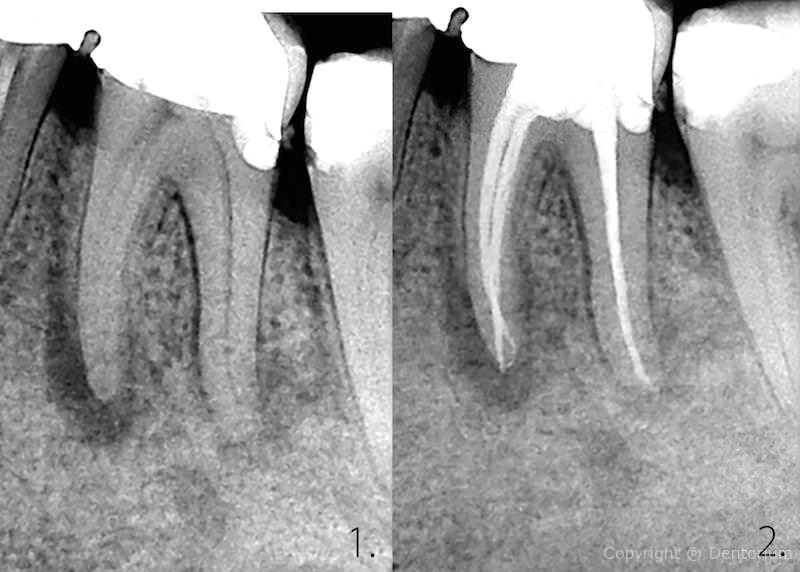

Il trattamento endodontico o trattamento canalare è necessario quando la polpa dentale è danneggiata dalle infezioni batteriche dalla carie o da trauma del dente.

- pulizia, allargamento e disinfezione del canale, somministrazione della medicina

- l’estrazione della medicina dentale, otturazione dei canali radicolari

Immediamente dopo il trattameneto si procede con RVG controllo del canale trattato.